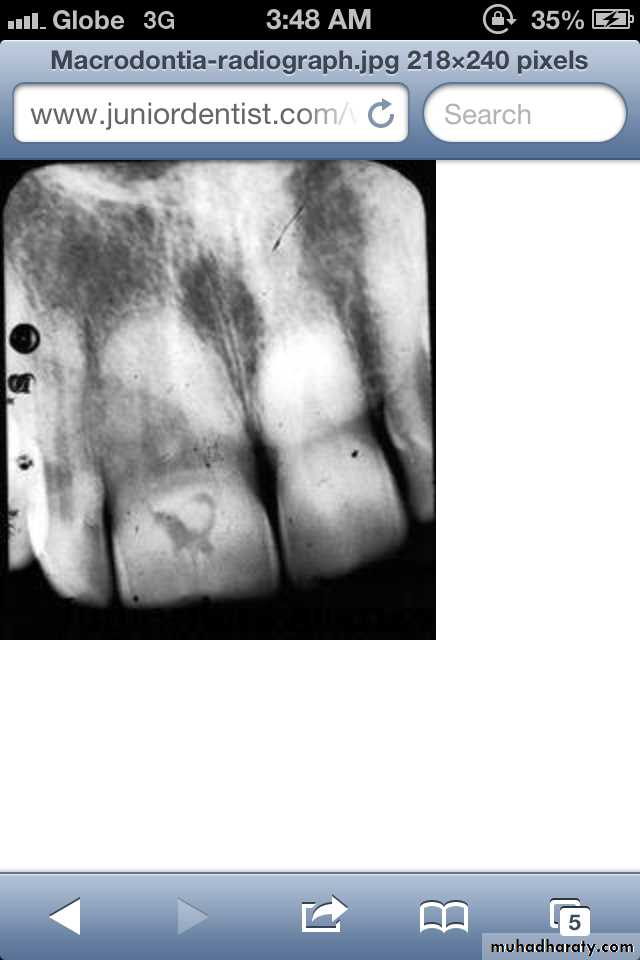

(1) True Generalized Macrodontia

all teeth are larger than normal.

associated with pituitary giantism.exceedingly rare.

(1) True Generalized Macrodontia: